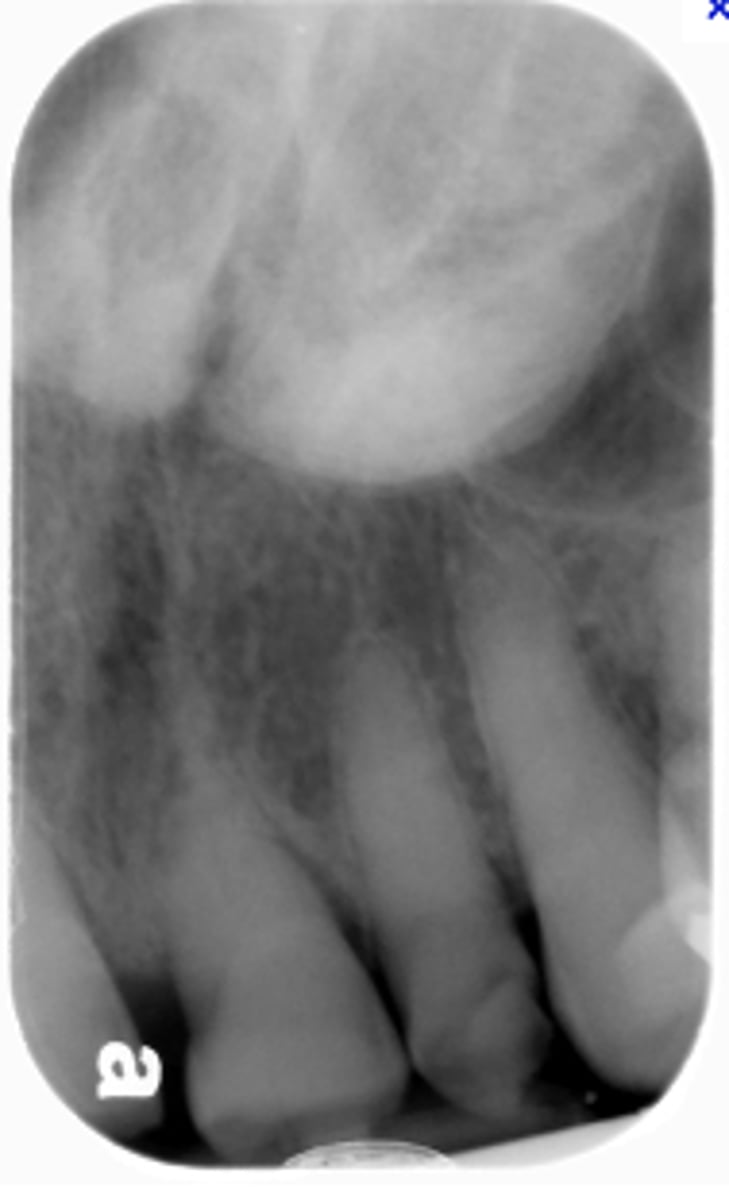

How would you describe the lesion?

- Defined corticated radiolucency associated with an impacted, displaced tooth

- Root resorption and teeth displacement also present along with thinning of the inferior mandibular cortex

- large calcifications noted just coronal to the impacted tooth

What category would this lesion be part of?

Benign

What would be a differential diagnosis for this lesion?

- Gorlins cyst

- Pindborg tumor